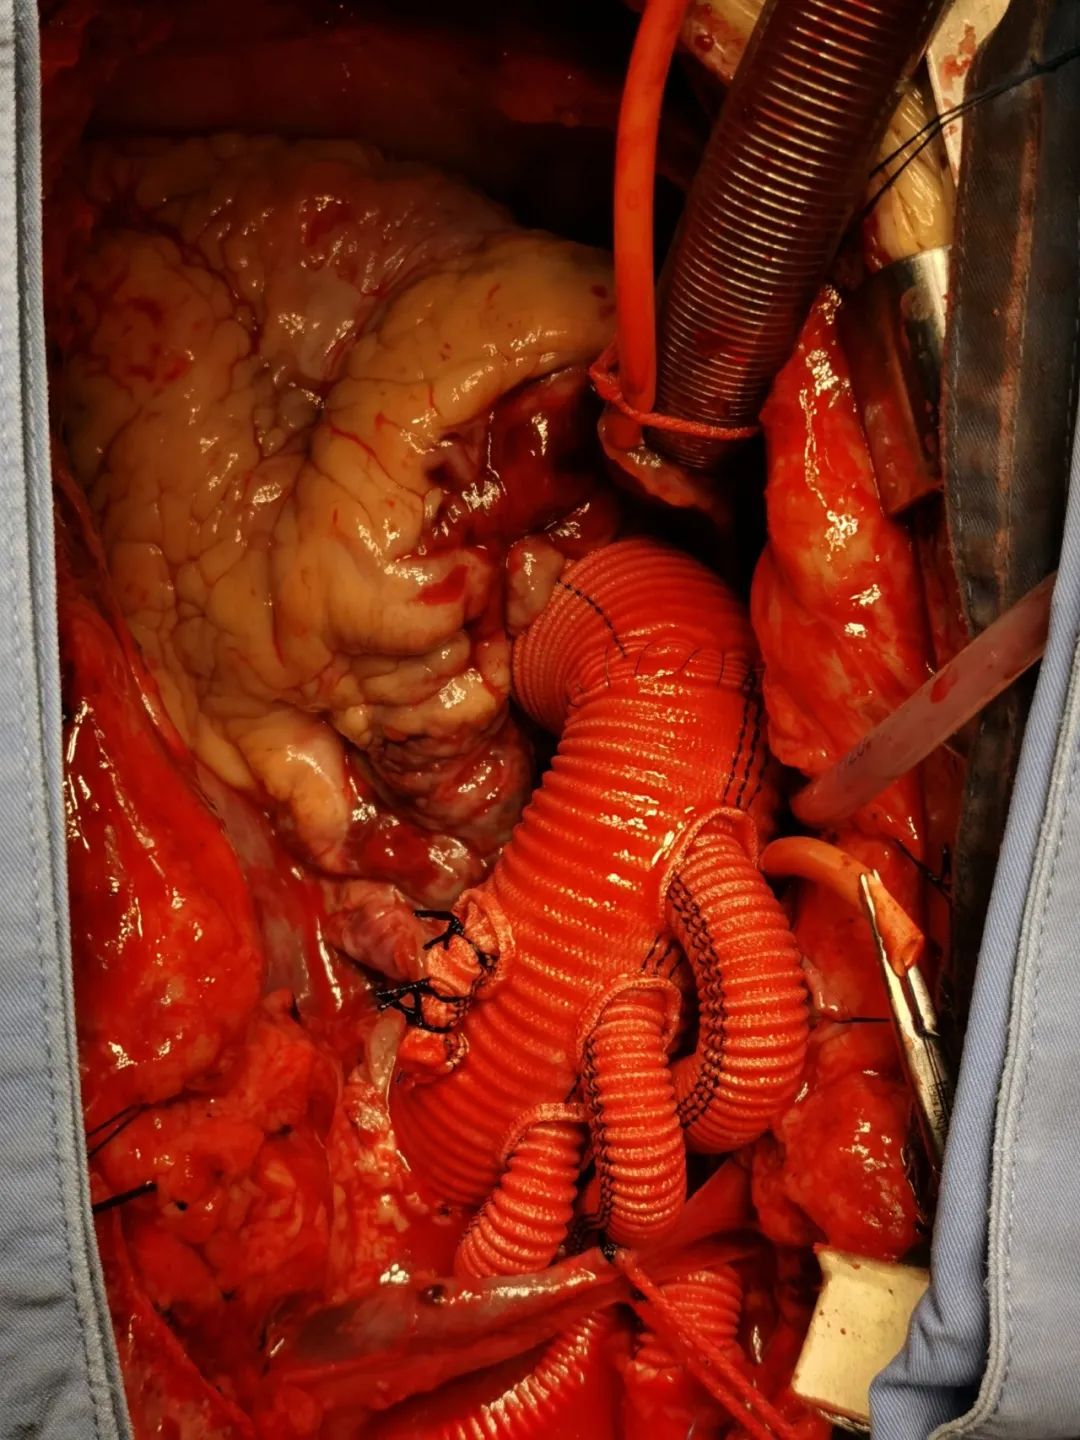

列入商议的有麻醉科、超声科、手术室、监护室及心脏大血管外科的医护人员,人人就这个病人纷纷揭橥了本身的定见,商议的核心还在手术的时机上,认为自动脉夹层的手术自己出血的风险就大,加之患者口服了两种冲击量的抗凝药物,如今手术出血的风险就更大了。而急性A型自动脉夹层是人类最凶险的疾病之一,在其发病后其灭亡率每小时增加1%,若患者发病48小时内不成急诊手术灭亡率为50%,2周内不手术病死率约75% 。对患者来说,灭亡随时降临。张晶副院长在综合人人的定见后,决意率领团队急诊给患者行手术治疗,“如今手术更能给患者带来生的进展!固然风险较其他夹层手术高”,张晶副院长如是说。 经与眷属充裕沟通,赞成手术!

一切都在心脏大血管外科团队医护人员的手下重要而有序地进行。手术历时9个小时,顺利完成“升自动脉置换+全弓置换+支架象鼻手术”。在医护人员的配合治理下,患者于术后12天顺利出院。全体医护人员都为患者和眷属感应由衷地愉快。